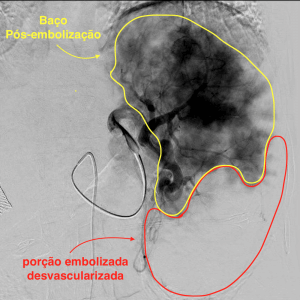

A Embolização esplênica é realizada durante um procedimento de arteriografia, também conhecido como “cateterismo”. Trata-se de um procedimento moderno, com utilização de recursos tecnológicos que permitem que a técnica seja realizada com apenas um pequeno furinho na virilha ou no punho, utilizando-se na grande maioria das vezes apenas anestesia local ou uma leve sedação.

Um pequeno cateter é introduzido por meio desse furinho, de forma indolor, e a partir desse cateter um outro cateter milimétrico é posicionado no interior das artérias do baço. Nos locais almejados, o médico Radiologista Intervencionista realiza a injeção de materiais sintéticos (ex: microesferas de gelatina) até ocasionar a interrupção do fluxo sanguíneo para uma parte do órgão. Como consequência, haverá uma redução controlada do tamanho do órgão e de sua funcionalidade, permitindo que aumente o número de plaquetas. Ao final do procedimento retiram-se os cateteres e é feito um curativo no local do furinho. Os pacientes submetidos à embolização costumam ficar internados em média por 12-24 horas no hospital.